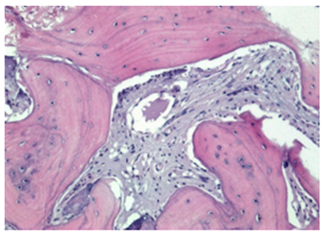

3.2. Histological Observation